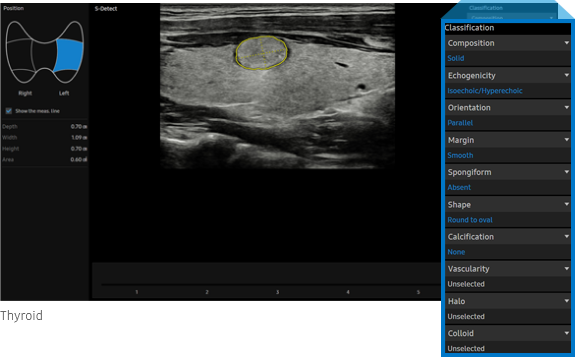

S-Detect™ ¹, ²  for Thyroid

Semi-automated imaging reporting tool for thyroid assessment

The feature, which analyzes selected lesions in the thyroid ultrasound study and shows the analysis data, provides standardized reporting based on the *ATA, BTA, EU-TIRADS, K-TIRADS and ACR TI-RADS guidelines; and helps diagnosis with the streamlined workflow.

• ATA: American Thyroid Association

BTA: British Thyroid Association

EU-TIRADS: European Thyroid Imaging, Reporting and Data System

K-TIRADS: Korean Thyroid Imaging, Reporting and Data System

ACR TI-RADS : American College of Radiology Thyroid Imaging,

Reporting and Data System

S-Detect for Thyroid